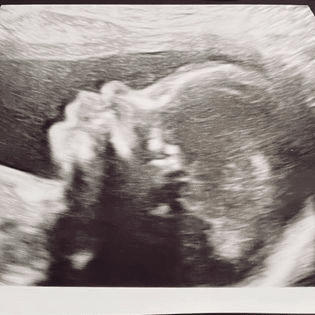

“Kindje met een megablaas”

Op de dag van de 12 weken echo gingen wij vol goede moed en vol vreugde naar de echo. Eindelijk echt een kindje zien i.p.v. alleen het knipperde hartje. We hadden er enorm veel zin in. De echo was in eerste instantie prima, we hoorde en zagen het hartje goed en regelmatig kloppen en alles zag er eigenlijk prima uit! De echoscopiste bleef wel wat over de blaas hangen; ‘hmm erg goed gevulde blaas…’ Ik dacht: ’top! Dat werkt dus ook!!’ ‘meid, ga maar even wat rondlopen, dan verwacht ik wel dat het kindje gaat plassen en dan kijken we over een half uurtje nog een keer’. Ok, nou ja, prima, maar wat is er dan aan de hand met die blaas dacht ik… hij is gevuld, dan doet ie het toch?

Een half uurtje later weer een echo, maar helaas had ons kindje nog niet geplast. Ze wilde er toch even een collega bij halen. Nou toen kreeg ik al een misselijk gevoel, maar ok, we wachten het af. Ook deze echoscopiste had twijfels bij de blaas ‘ja, hij is voor deze termijn wel erg goed gevuld, ik vraag dr. (weet ik niet meer) om ook even mee te kijken. Mij werd nog niets verteld, de echoscopiste probeerde me gerust te stellen, maar dat lukte niet erg. De gynaecoloog maakte ook een echo en was ook duidelijk wel ongerust.